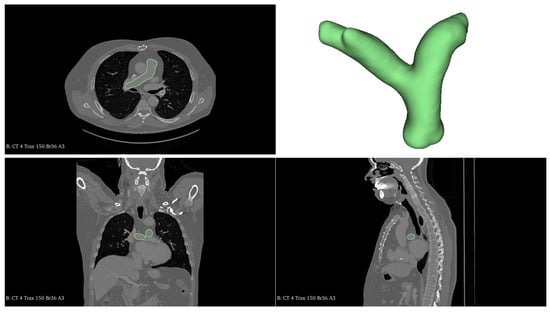

Patient-Specific Computational Hemodynamic Modeling of the Right Pulmonary Artery Using CardioMEMS Data: Validation, Simplification, and Sensitivity Analysis

by Angélica Casero, Laura G. Sánchez, Felicia Alfano, Pedro Navas, Juan F. Oteo, Carlos Arellano-Serrano and Manuel Gómez-Bueno

Fluids 2026, 11(3), 83; https://doi.org/10.3390/fluids11030083 - 19 Mar 2026

This study investigates the application of computational hemodynamic modeling, involving both FSI and CFD models, using SimVascular to simulate blood flow in the right pulmonary artery for patient-specific cardiovascular assessment. The artery’s three-dimensional geometry was reconstructed from a computed tomography (CT) image, and [...] Read more.

This study investigates the application of computational hemodynamic modeling, involving both FSI and CFD models, using SimVascular to simulate blood flow in the right pulmonary artery for patient-specific cardiovascular assessment. The artery’s three-dimensional geometry was reconstructed from a computed tomography (CT) image, and pressure measurements from a CardioMEMS™ device were used as clinical ground truth for validation. To represent the arterial hemodynamics, we initially formulated a fluid–structure interaction (FSI) approach to capture wall mechanics. However, given the high computational cost of fully patient-specific FSI simulations for routine clinical decision-making, we evaluated the validity of key simplifications by assuming rigid vessel walls coupled with a three-element Windkessel (3WK) model and applying a half-sine inflow waveform derived from the patient’s cardiac output. These simplifications yielded results with minimal error: the rigid-wall assumption introduced a 1.1% deviation, while the idealized waveform resulted in a 0.56 mmHg offset. Crucially, while wall rigidity was acceptable, we found that arterial compliance in the boundary conditions is non-negotiable; reducing the model to a pure resistance approach resulted in non-physiological pressures (130 mmHg). A subsequent parametric analysis examined how varying resistance (R) and compliance (C) distinctively alter the pressure waveform morphology. The results underscore the potential of combining remote monitoring data with validated computational simulations to deepen the understanding of cardiovascular dynamics and enhance diagnostic and therapeutic approaches for cardiovascular diseases. Full article